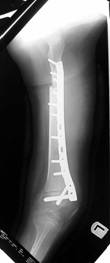

Left tibia lengthening with fixator in place

Lengthening tibia on Xrays in progress

Lengthening proceeding

Converted to immediate exchane nail after 65mm lengthening

Consolidation regenerated